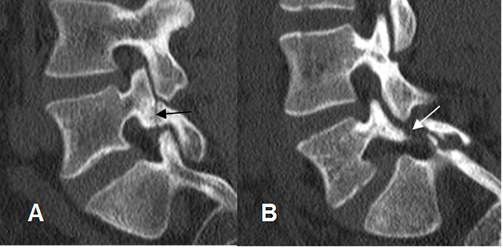

Se aprecia como imagen radiolúcida en la pars interarticular, con esclerosis de los fragmentos, mejor visto en una Rx oblicua. Puede ser uni o bilateral. En la TAC se encuentran los mismos hallazgos, en cortes por encima del nivel del disco. (1). (Fig 72 a 74).

Fig 74. Listesis.

A y B: TAC reconstrucción sagital. Listesis sin desplazamiento en A y desplazada en B.